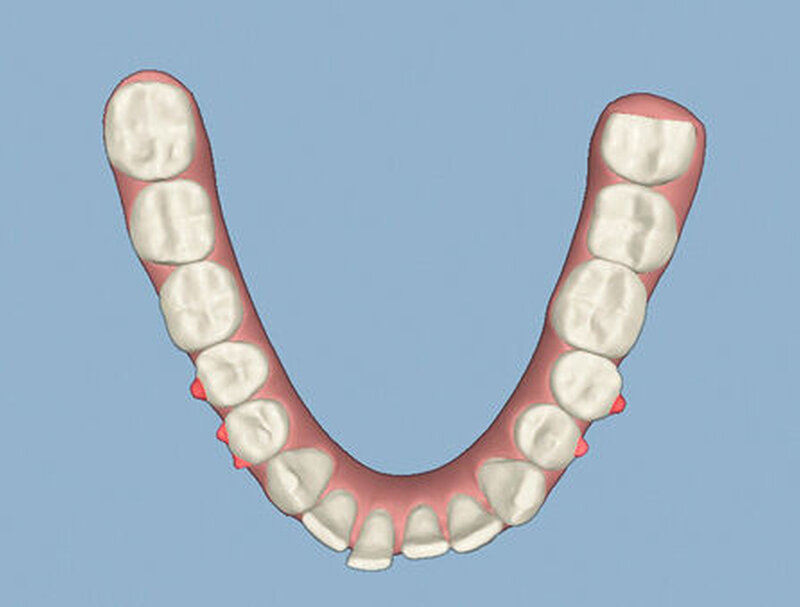

Die Sulkustiefen konnten auf etwas weniger als 4 mm reduziert werden, während der Blutungs- und Plaque-Index bei weniger als 15 Prozent lag. Daher wurde eine kieferorthopädische Behandlung über die nächsten zwei Jahre in Kombination mit engen zahnärztlichen Kontrollen geplant. Als Mittel der Wahl entschieden wir uns gemeinsam mit dem Patienten für das Invisalign-System, da hiermit sowohl eine Schienung als auch eine kraft-arme Bewegung der Zähne möglich sein sollte. Für den Frontzahnbereich wurden keine Attachments geplant, so dass hier eine unnötige Hebelwirkung umgangen werden konnte (Abbildung 3).

Um einen kompletten Lückenschluss im Oberkiefer zu ermöglichen, musste im Unterkieferfrontzahnbereich zusätzlich zur Derotation und Positionierung der Zähne – insbesondere Zahn 41 – von approximaler Schmelzreduktion, kurz ASR , Gebrauch gemacht werden, um einer Tonn`schen Diskrepanz entgegenzuwirken (siehe dazu Abbildung 7 auf Seite xy).